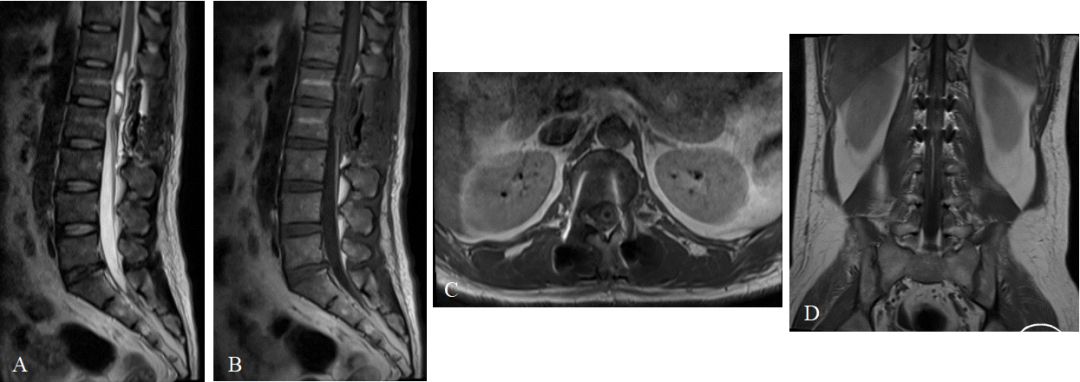

术后MRI:腰1、腰2椎体可见横行内固定金属伪影,胸12-腰2椎体水平脊髓内可见条状长T2信号,范围较术前明显缩小,增强扫描未见异常强化(图4)。

图4. 术后MRI检查。A . T2WI 矢状位;B.增强矢状位;C.增强轴位;D. 增强冠状位